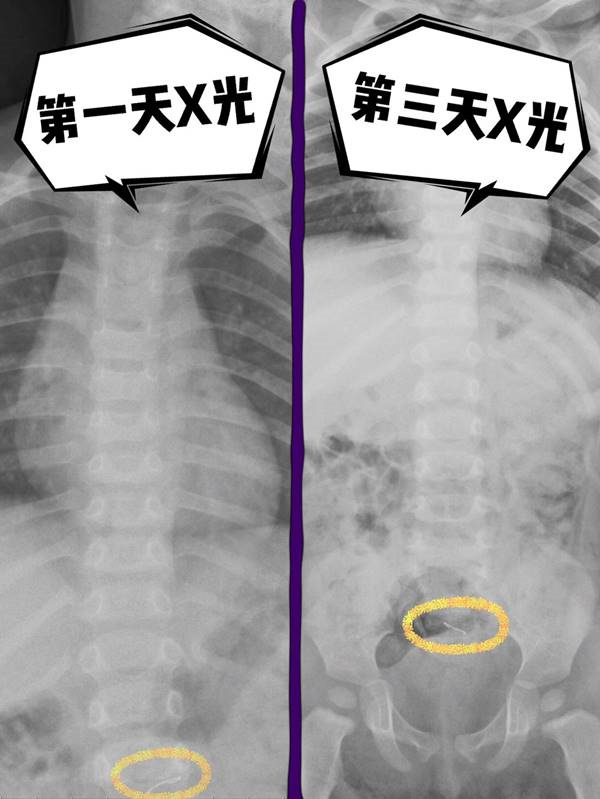

2岁的宝宝吞食硬币和磁珠,导致了肠穿孔,家长们需要警惕!

9月龄宝宝误吞巴克球导致肠穿孔